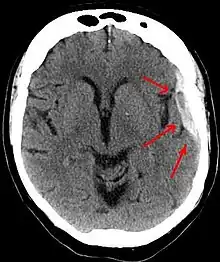

![]() Subduralt hæmatom vist med pile med betydelig midtlinjeforskydning. | |

Diagnosen stilles typisk ved CT-scanning af hovedet. Alternativt kan MR-scanning bruges. SDHer opstår oftest over frontal- eller temporallapperne.[3][8] De kan også forekomme i kraniets fossa posterior, ved falx cerebri og tentorium cerebelli.[3]

På en CT-skanning kan et SDH ses som en linseformet bramme med den konkave side mod hjernen. I den akutte fase ses det friske blod som klart hvidt på billederne, men senere vil den gå over i lysegrå i takt med at blodet reabsorberes. Til forskel for epidurale blødninger er SDHer ikke afgrænset af kraniets suturer og vil derfor brede sig over en større del af hjernens overflade. På hjernens overflade, umiddelbart under blødningen, kan der være hypodensitet (mørkfarvning) af hjernevævet, som tegn på iskæmi og medfølgende væskeansamling.